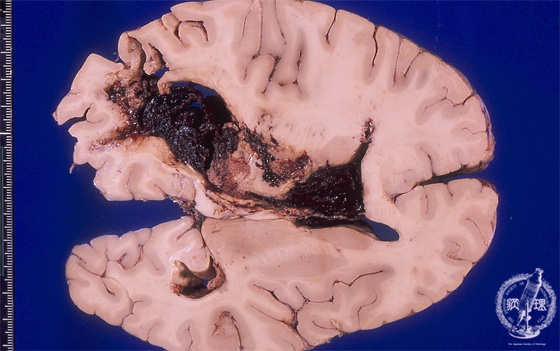

Macroscopic findings (left thalamic hemorrhage): A case of hypertensive hemorrhage ruptured into a lateral ventricle. Thalamic hemorrhage more marked than putamen hemorrhage due to its relatively high tendency of rupture to the ventricle.

Click the image to see the enlarged image.